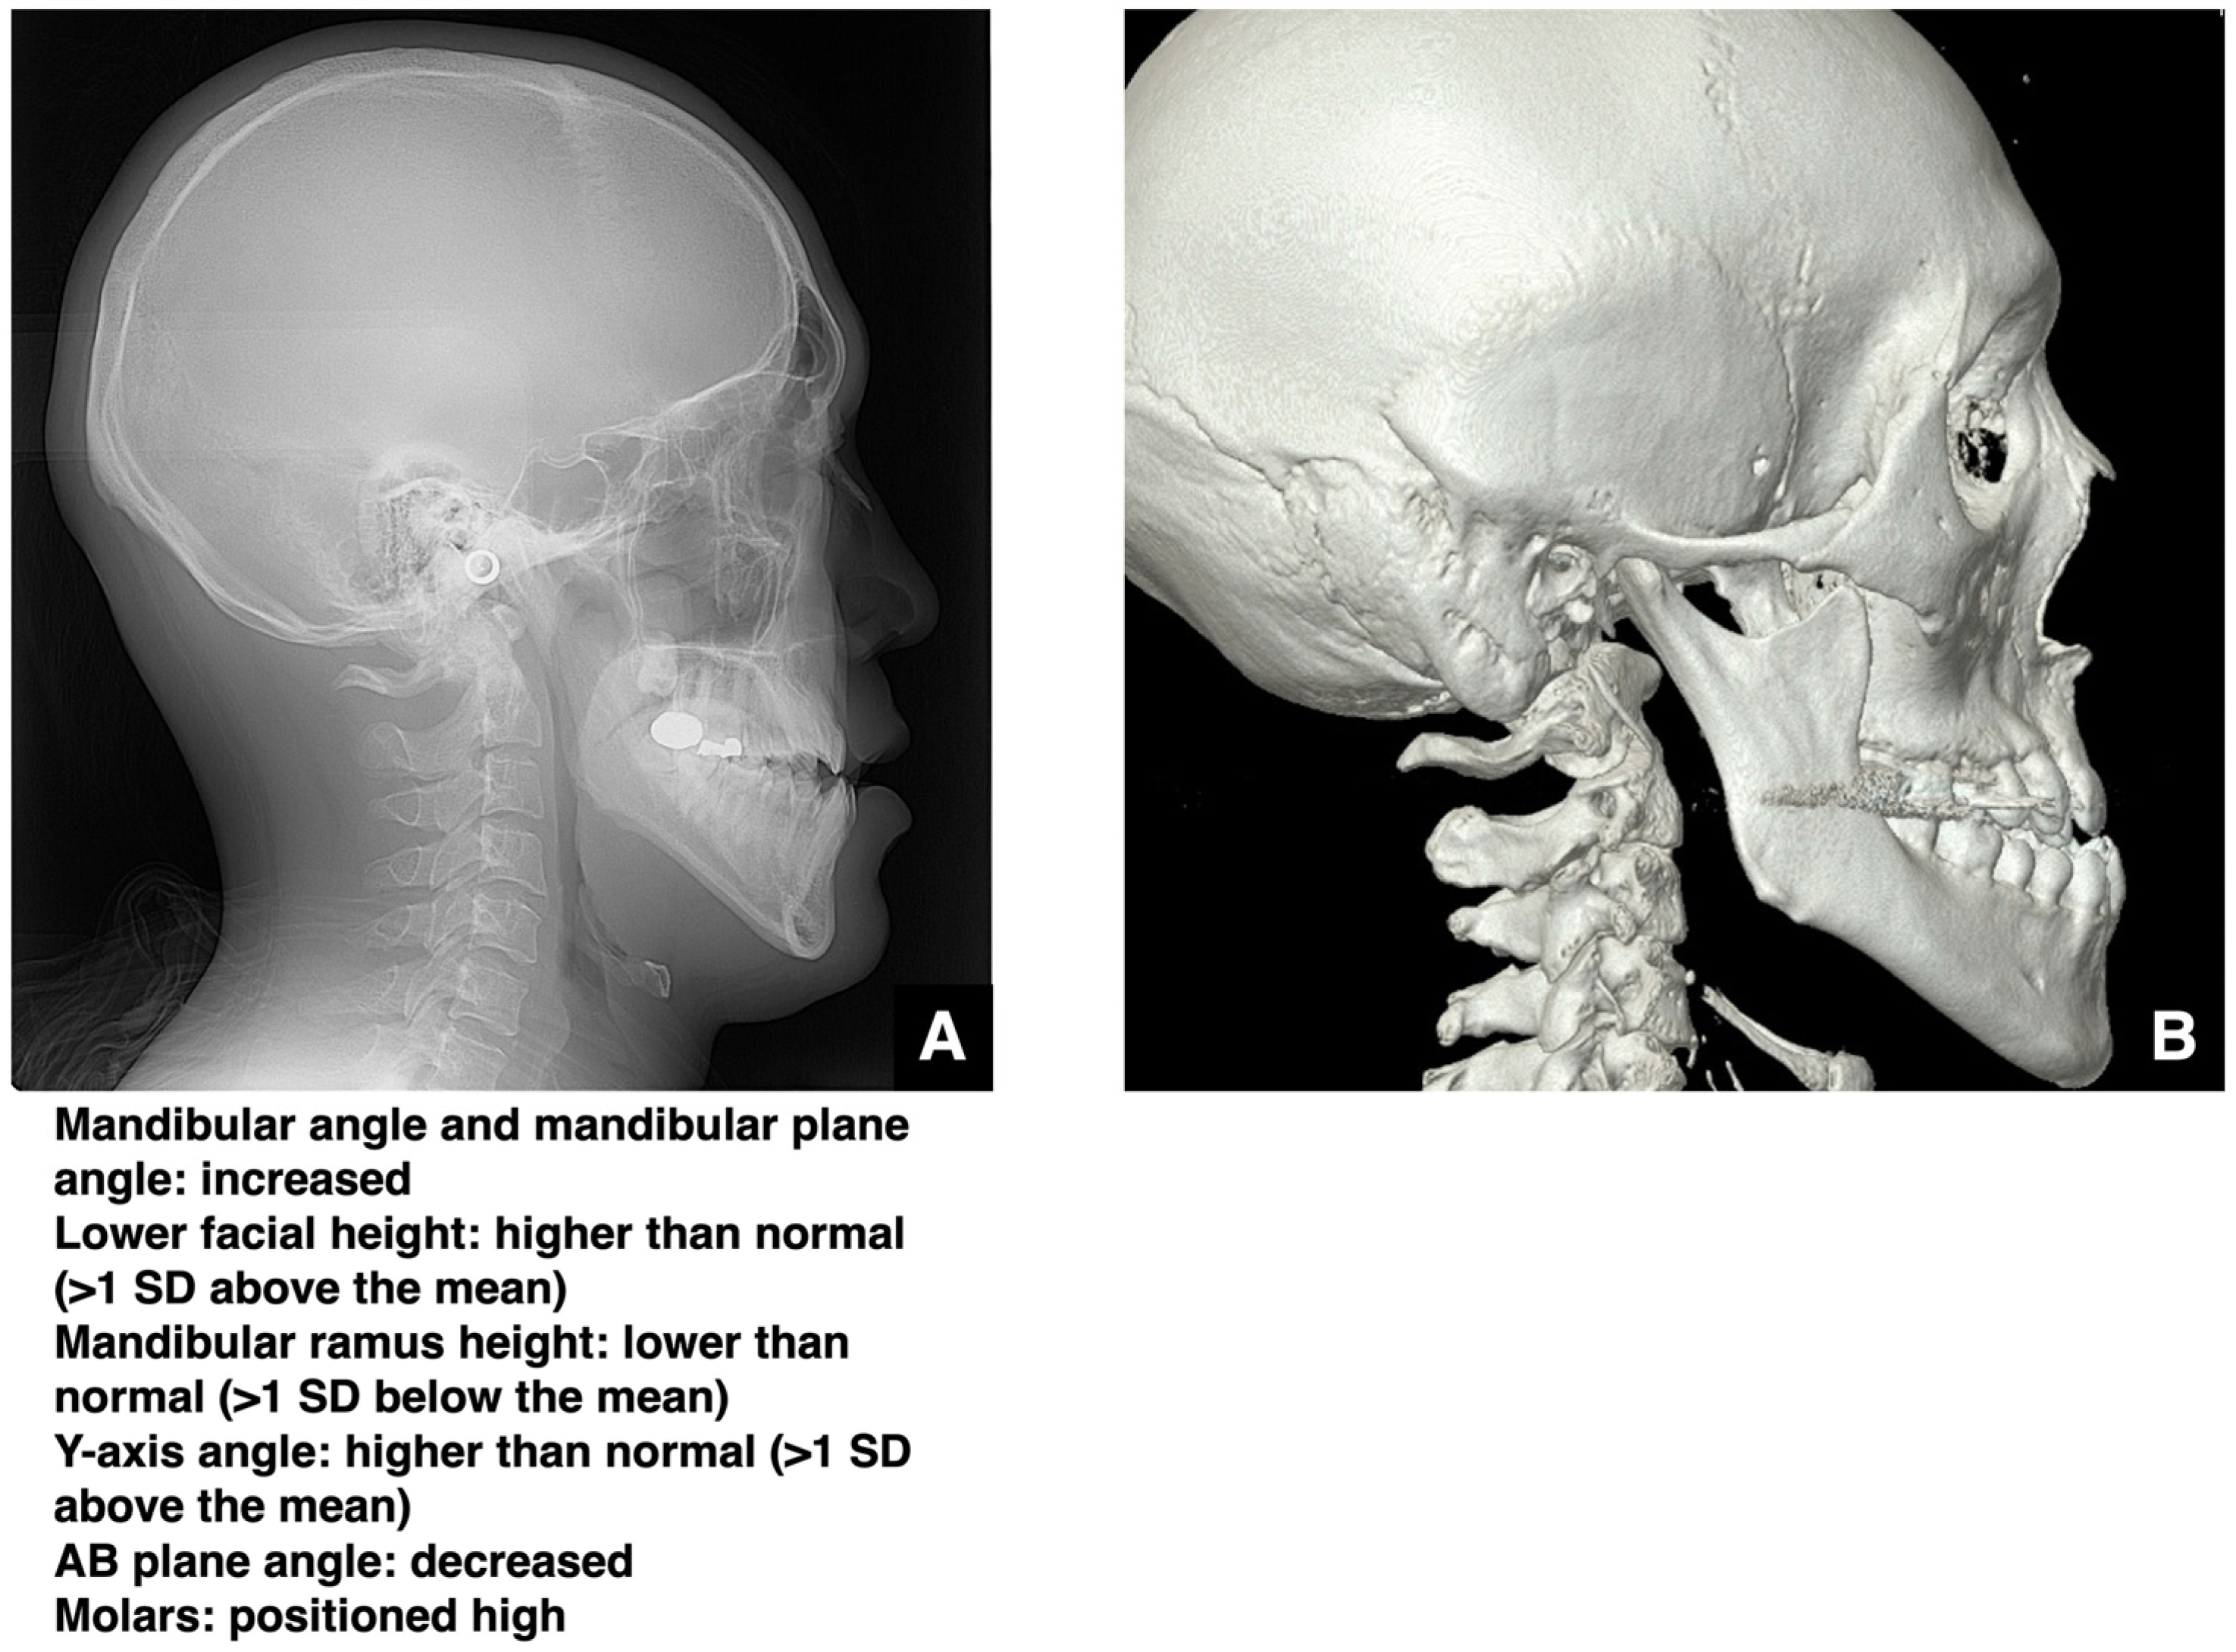

| Enhanced safety through improved visibility 1. Course of the submental artery and its branches Identification of the submandibular gland and its medial aspect 2. Course of the sublingual artery and the mental nerve Identification of the mentalis muscle, hyoglossus muscle, and anterior belly of the digastric muscle and their medial aspects (Observed within the fatty tissue beneath the chin) 3. Course of small blood vessels along the bone surface Degree of looping at the mentum foramen during opening, course of the incisive branch Setting the osteotomy line 1. Position of the mental foramen and course of the incisive branch Record the position of each root for each lower tooth 2. Position of the mandibular anterior tooth roots Record the thickness of the cortical bone using the mandibular teeth as a reference point 3. Variation in cortical bone thickness in the anterior mandible Depression of the cortical bone in the mandibular anterior region, trabecular bone defect |